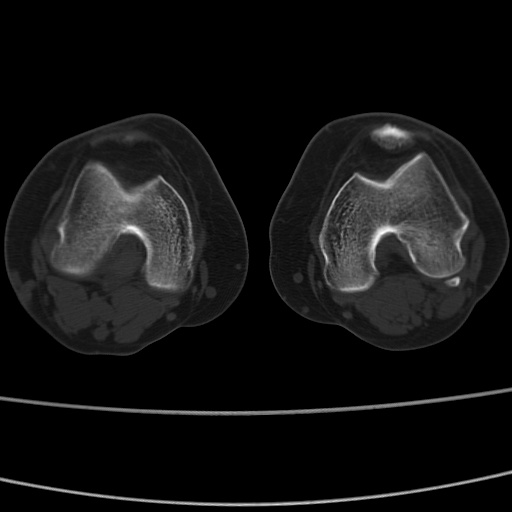

女性,50岁。【请提供患者临床症状体征】

右膝关节退行性改变,关节游离鼠。

右膝关节退行性改变,滑膜黏液囊钙/骨化并游离。

右膝关节退行性改变